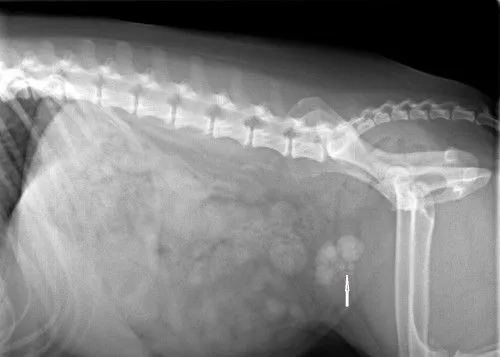

After Surgery